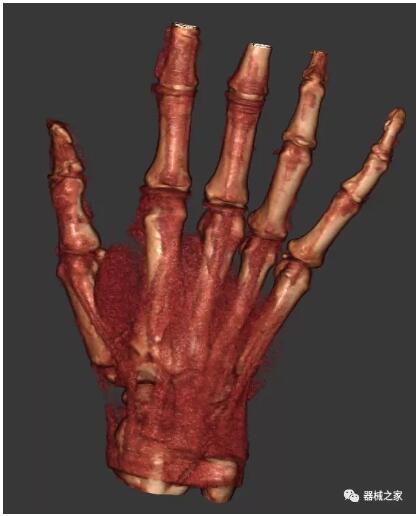

另外一款被稱為世界上最小的CT,它的重量僅300磅,不僅能夠掃查足部,還可以檢查膝蓋和上肢等。

與上面介紹的CT一樣,它同樣具有輻射低、占地空間?。?3*36)的特點,隨開隨用(支持直接接入墻上的插座)。

這款CT使用非常方便,通過上下移動保持與患者的手臂或者雙腿齊平,掃描快速,僅需要30秒左右就可以完成掃查。

以下是這些“特立獨行”的CT所拍出來的圖像: